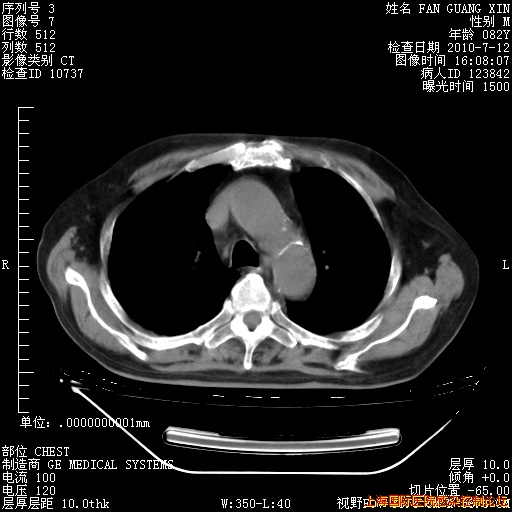

今天复查CT

今天CT

整整相隔30天的肺部CT好像有所好转啊。甲强龙减量第3天,需要观察体温。